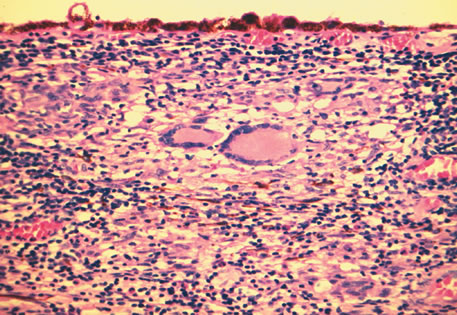

Inflammatory conditions may also lead to iris nodules. Patients suffering from fungal endophthalmitis may demonstrate an irregular yellow-white mass on the iris. Histologically, these appear as necrotizing granulomas containing mycotic agents (Fig. 2). In juvenile xanthogranuloma, a yellowish-gray iris lesion may be associated with spontaneous hyphema, and histopathologically the nodules demonstrate diffuse histiocytic infiltrate (Fig. 3). Multinucleated giant cells displaying peripheral foamy cytoplasm are also noted; these cells are known as Touton giant cells.29 The giant cells and the histiocytes contain lipid that can be demonstrated by oil red O stain.

Fig. 2. Coccidioidomycosis. Iris stroma shows necrotizing granuloma containing mycotic organisms. The organisms show features of Coccidioides immitis. (Hemotoxylin-eosin ×60.)